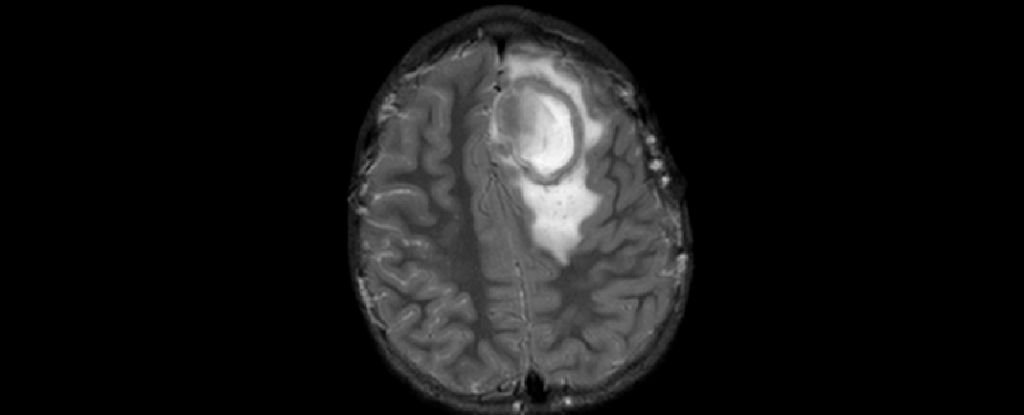

A brain abscess occurs when bacteria or other pathogens infect the brain, forming a pocket of pus. In children, these infections often start as routine sinusitis or ear infections that travel to the brain. Though rare, brain abscesses are considered medical emergencies because they can rapidly worsen if untreated. Early recognition and treatment are critical to preventing complications and promoting full recovery.

Brain abscesses usually occur when an infection in another part of the body, such as the sinuses or ears, spreads to the brain. The immune system often contains infections in children, but under certain conditions, bacteria can travel through the bloodstream or directly invade brain tissue. Children recovering from severe viral infections are at higher risk, as viral illness can weaken local defenses and make the brain more vulnerable to secondary bacterial invasion. https://my.clevelandclinic.org/health/diseases/21777-brain-abscess

Recognizing early brain abscess symptoms in children is crucial. Common warning signs include persistent headache, swelling around the eyes, fever, nausea, and neurological symptoms such as seizures or weakness. Parents should seek prompt medical attention if a child exhibits these symptoms, especially following a recent sinus or ear infection. Pediatric specialists emphasize that timely diagnosis can significantly improve outcomes.